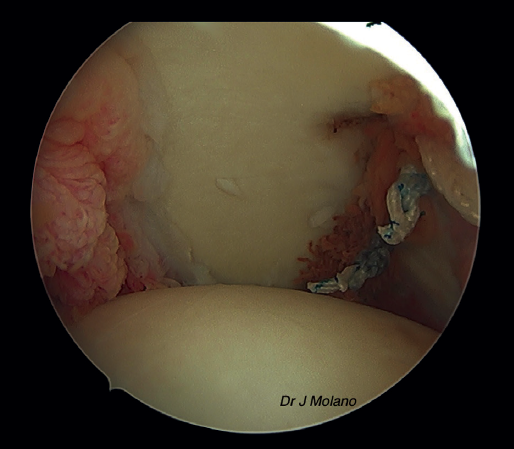

Figura 3. Visión artroscópica desde el portal superior de un hombro derecho. Se observa Hill-Sachs tras pasar las suturas de remplissage, antes del anudado final.

Posteriormente, se realiza el remplissage por vía artroscópica. Se coloca el artroscopio en el portal anterosuperior y se emplean el anterior y el posterior como portales de trabajo. Desde el portal posterior se realiza el curetaje/raspado superficial de la lesión de Hill-Sachs para conseguir una superficie sangrante. Tras ello, se colocan 2 implantes de tipo Iconix® (Stryker, Kalamazoo, MI, USA) (cargados con 2 hilos de sutura cada uno) desde el portal posterior próximos a la parte más medial del defecto de Hill-Sachs. Se recupera cada cabo de sutura de manera independiente a través del tejido capsular/infraespinoso con una pinza grasper, quedando estos en la misma línea mediolateral para ser anudadas sobre el infraespinoso al final del tiempo artroscópico(14) (Figuras 2 y 3).